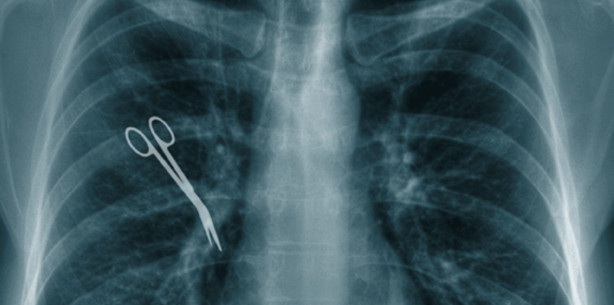

Nach Operation 16 Fremdkörper in Patient entdeckt

Foto: © Lukasz Panek - Fotolia.com

Nach einer Operation in einer Klinik in Hannover sind im Körper eines Mannes 16 Fremdkörper entdeckt worden. Darunter waren eine OP-Nadel und diverses Verbandsmaterial, sagte Medizinrechtler Annette Corinth, die die Hinterbliebenen des Patienten vertritt, der Nachrichtenagentur dpa am Montag. «Ein solches Ausmaß von Fremdkörpern, die nach einer OP im Körper vergessen wurden, ist in der medizinischen Fachliteratur einmalig.» Der Mann war im April 2012 gestorben. Zuvor hatten bereits andere Medien wie der «Spiegel» oder die «Hannoversche Allgemeine Zeitung» von dem Fall berichtet.

Entdeckt wurden die Gegenstände Monate nach der Operation im Henriettenstift in Hannover, wo dem 74-Jährigen ein künstlicher Darmausgang gelegt wurde. Seit 2010 gibt es Streit um Schmerzensgeld. Der Hausarzt attestierte ihm, dass die groben Behandlungsfehler entscheidend zu seinem schlechten Zustand beigetragen hätten.

Die Versicherung der Klinik und des operierenden Arztes, die VGH, bot dem Mann zunächst nur 500 Euro Schmerzensgeld. «Das ist ein Skandal», sagte die Anwältin. Inzwischen werden den Hinterbliebenen 15 000 Euro geboten. Dies sei aber nicht als generelles Schuldeingeständnis zu werten, erklärte die VDH. «Wir haben der Anwältin diverse Angebote unterbreitet», sagte eine Sprecherin. Von der Klinik war zunächst keine Stellungnahme zu bekommen.